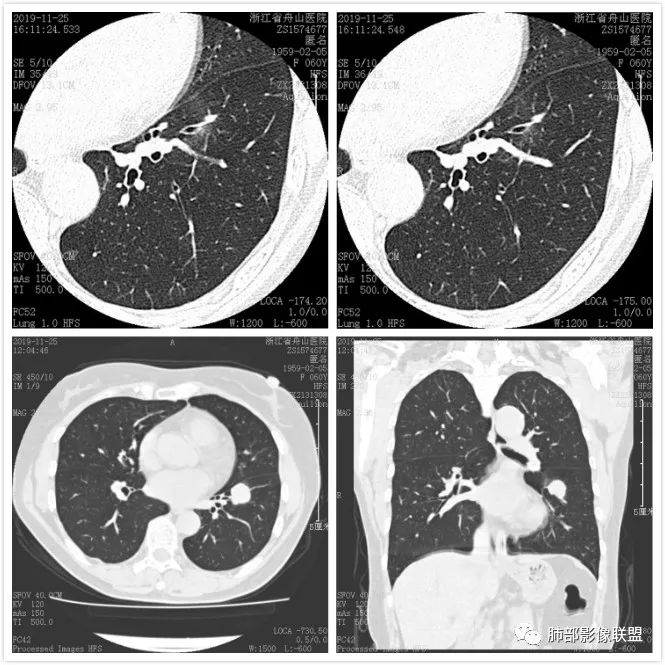

肺腺癌1例CT影像讨论

图像资料

这个病例看上去像个爱心,但是具备恶性征象不少,有分叶,脐凹,支气管截断,膨隆,月牙铲等。没有毛刺,牵拉力不强,多见于低分化肿瘤,其收缩力可以消失,特别是实体型。实体型内部纤维组织很少。与不典型类癌鉴别比较难,典型类癌分叶不明显;不典型类癌男女比例差不多,少见。

图一:提示支气管截断;图二:看到脐凹血管进入;图三:月牙铲;图四:典型分叶;图五:病灶膨隆,图六:支气管截断可能。 医学百科网 | YxBaike.Com